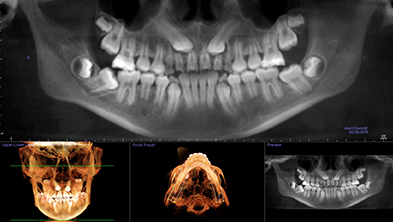

Radiografía 3D con caninos incluidos, retenidos y molar angulado